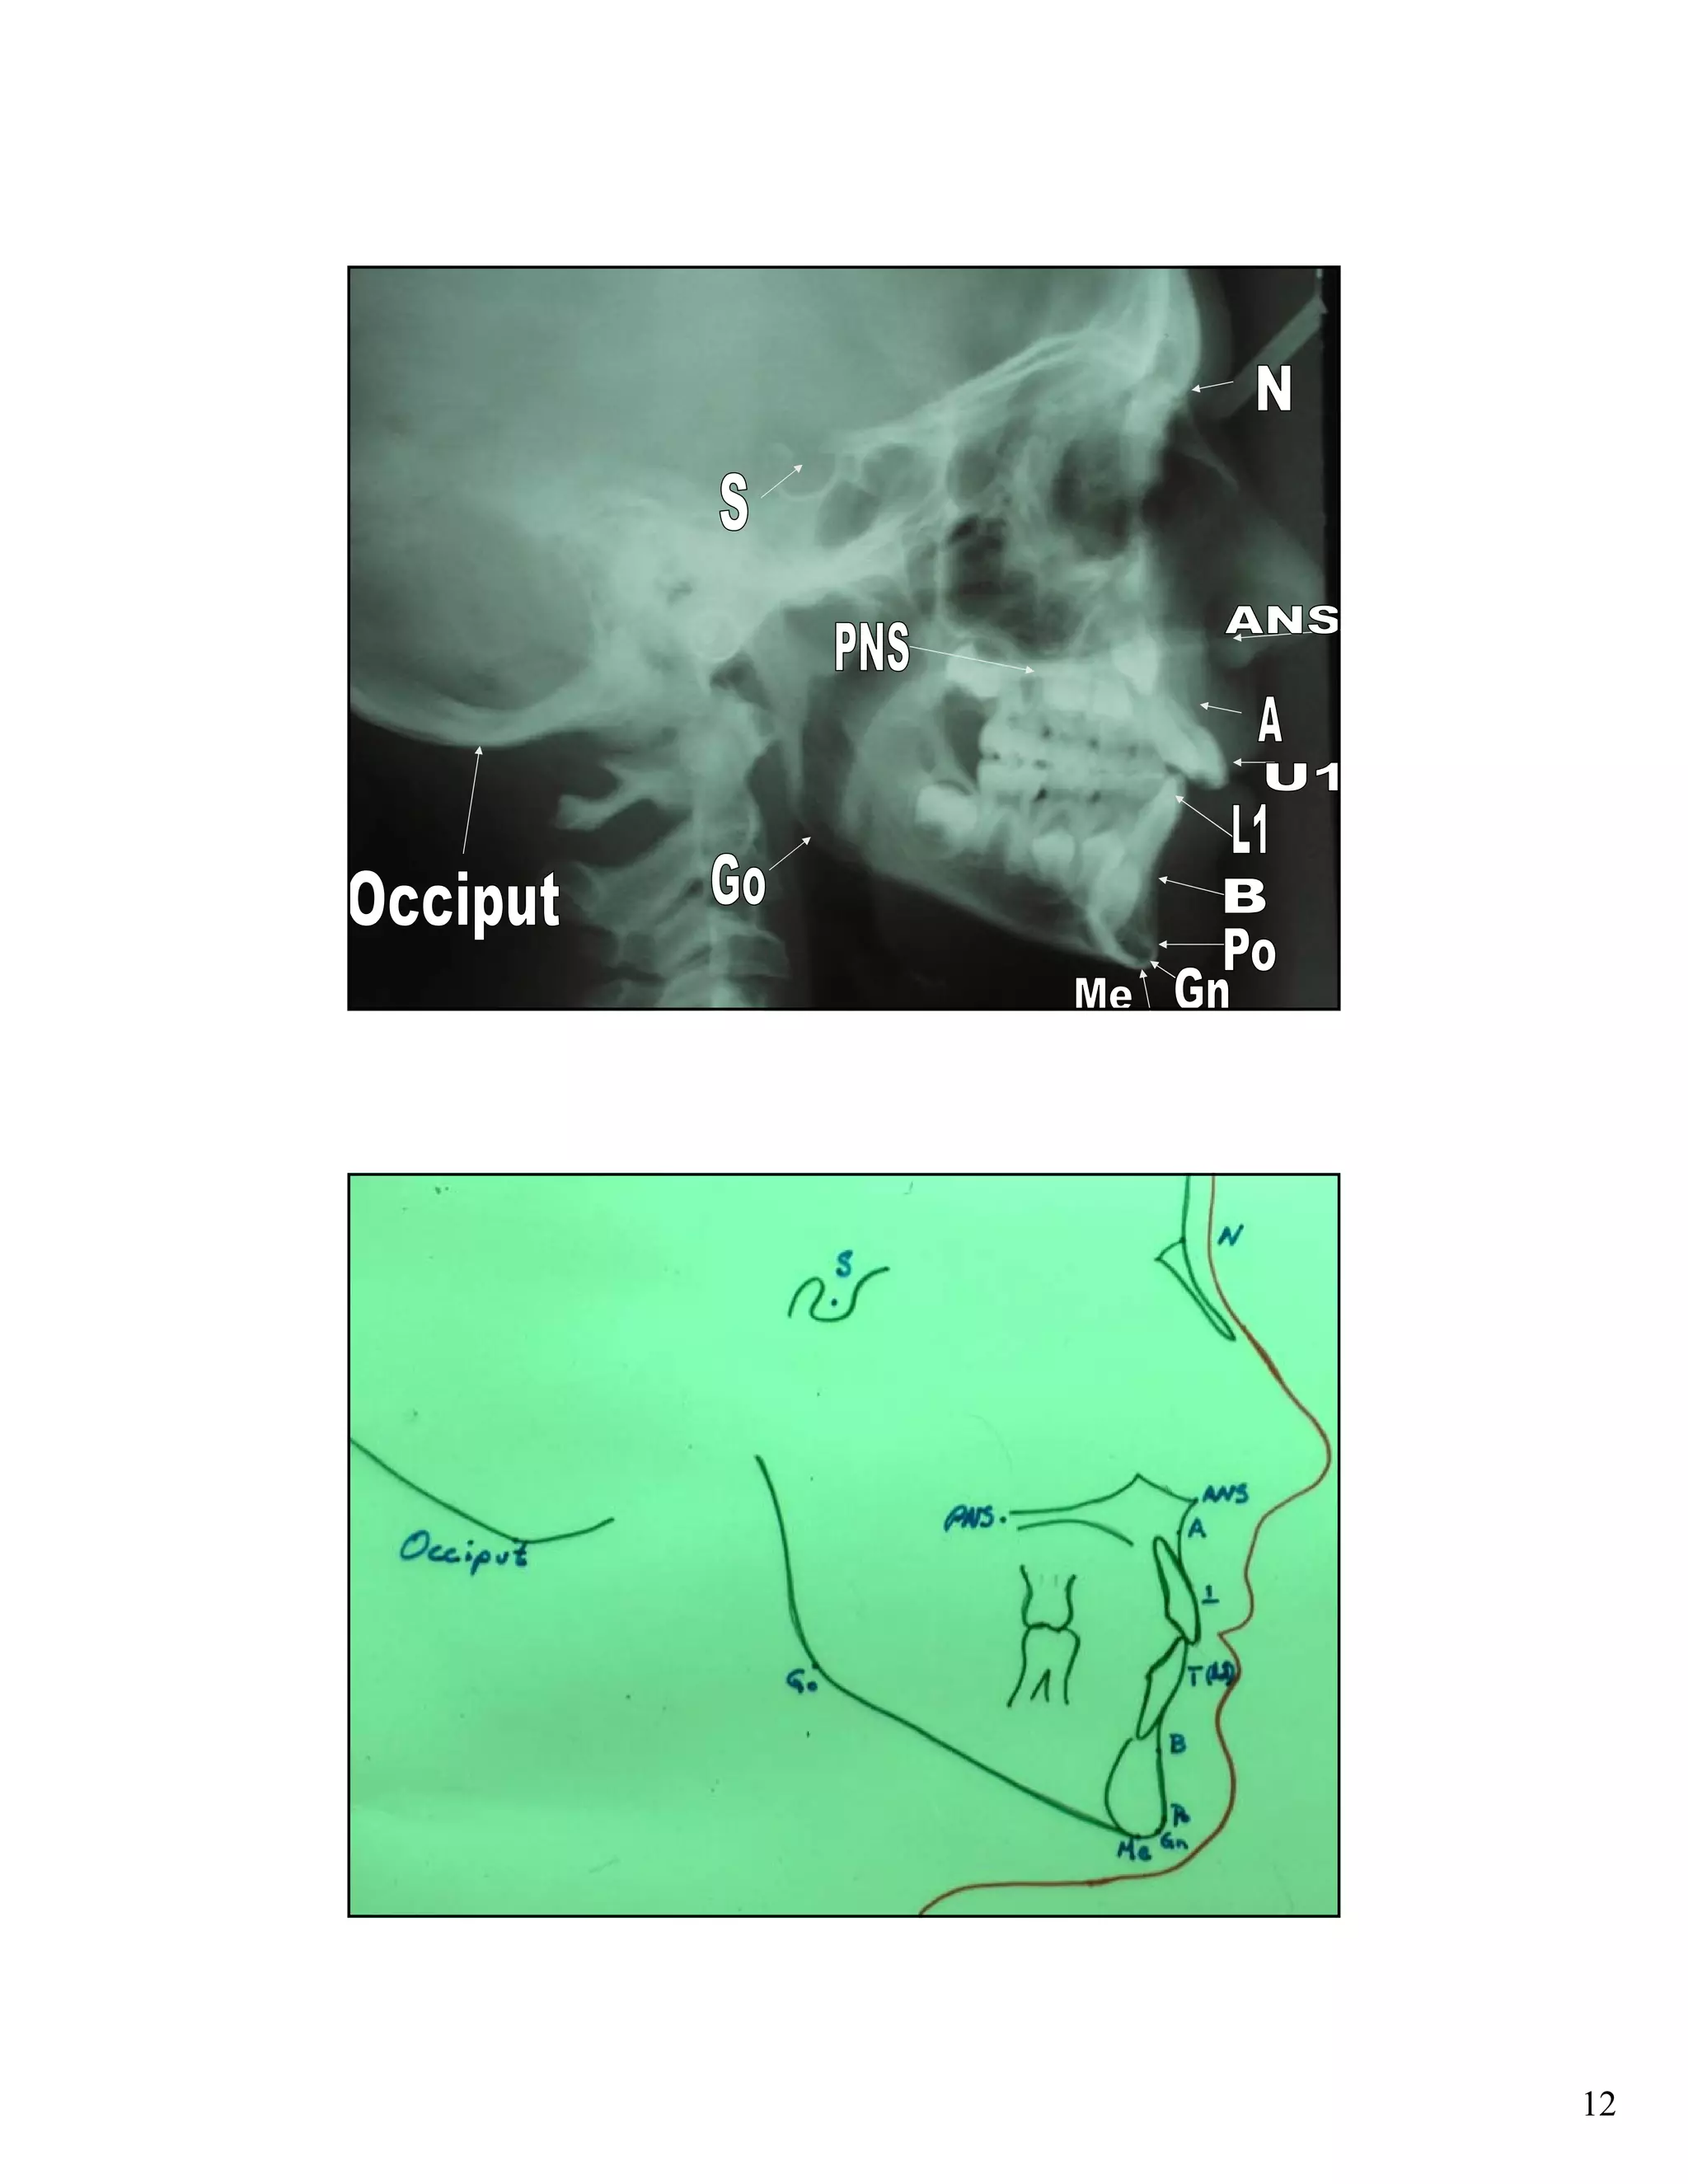

Cephalometric analysis uses x-rays of the skull to measure the growth and development of facial structures. Key indicators include the SN:GoGn angle measuring lower facial growth direction, the S-Go/N-Me ratio comparing posterior and anterior facial heights, and extension of the GoGn line to the occiput. These measurements help assess growth trends and plan orthodontic treatments.